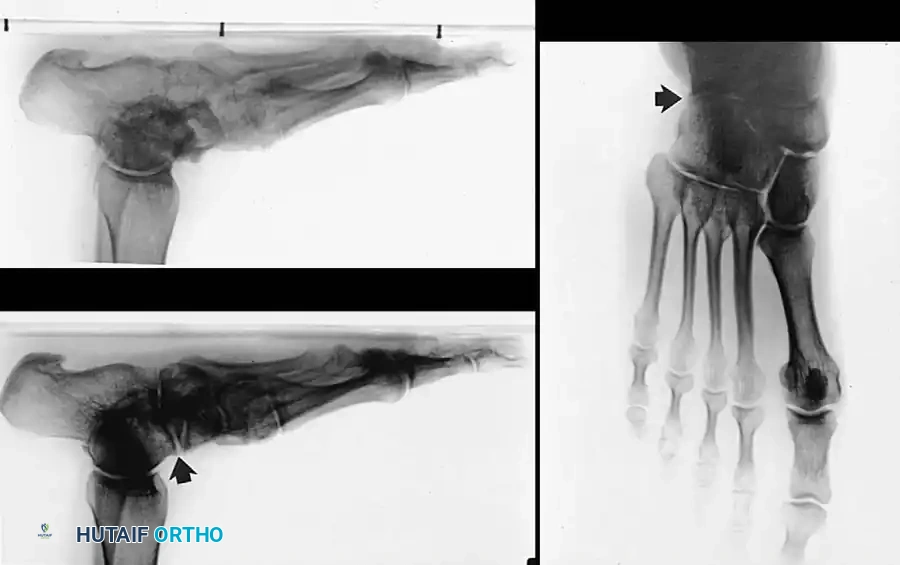

Standing radiographs in the anteroposterior (AP) and lateral planes, alongside nonstanding lateral oblique views, are mandatory to evaluate the severity of the deformity.

On the dorsoplantar (AP) view, talocalcaneal divergence (Kite's angle) is increased, and talonavicular uncoverage is evident. On the lateral view, plantar flexion of the talus disrupts Meary’s line (the talar-first metatarsal axis). Lateur et al. (1994) described the “C” sign on lateral radiographs of the ankle as suggestive of a talocalcaneal subtalar coalition. While highly useful, Brown et al. later found the “C” sign to be more specific for severe pes planus than for subtalar coalition alone.

Additionally, a structural “sag” at the talonavicular, naviculocuneiform, or tarsometatarsal joints can be assessed. The oblique view in a 9- to 14-year-old child is critical, as it may reveal a calcaneonavicular bony bar or suggest a synchondrosis.